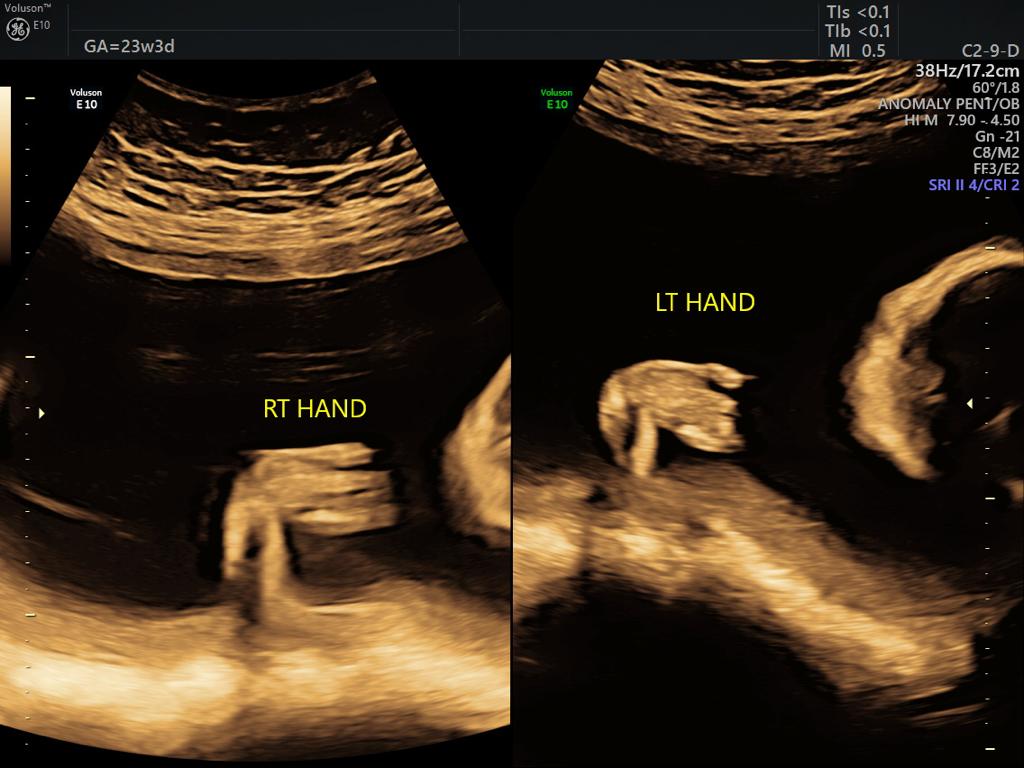

One of the most important scans done during pregnancy is during the second trimester, between weeks 18 and 20. This is called the targeted anomaly scan and is essentially a complete head to toe analysis of the fetus in a clinical perspective. Even though the scan might not be able to identify every single issue, however, gynaecology specialists in Guntur use this scan to validate and rule out any discrepancies with respect to most of the major organs in the Childs body including the brain, kidneys, bones, heart as well as the spinal cord and face, etc. The measurements with respect to every organ are taken also another important aspect of this scan is to identify how the placenta is placed and if it is tending towards creating an issue later on. Visit ultra sound test centers in Guntur at fertility hospitals.

• Organs status: This scan is also used to check if all the organs are formed properly.

Sometimes improper growth could be a cause of concern and on the other side, there are certain disorders which are identified in this scan, some could be rare congenital heart anomalies related to fetalbrain,face, thorax,heart,GIT,renal, skeletal etc